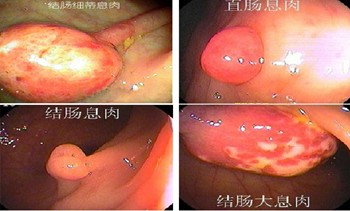

肠息肉,顾名思义,就是肠道上向外突出的赘生物,肠息肉按照发病位置的不同,可分为结肠息肉和直肠息肉,这两者的具体症状是有所差异的,下文中,医生通过图片的形式进行了详细讲解。

结肠息肉的症状有什么?

直肠息肉的症状有什么?